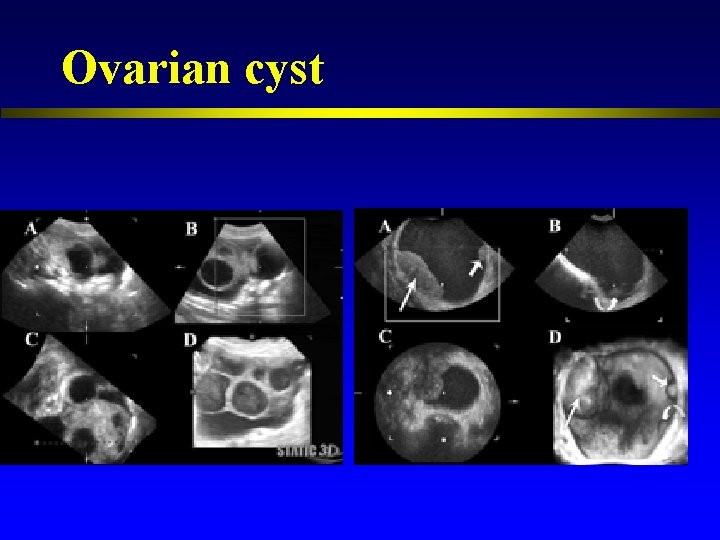

Ovarian cyst